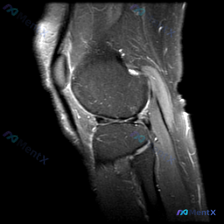

号称是软骨异常的膝关节MRI,我看了半天没发现明确病变?来聊聊这个尴尬的情况

拿到这个病例:核心问题是「这张膝关节MRI里的软骨异常在哪里?」,先把读片结果和思路整理给大家。

这是一张单张膝关节矢状位MRI,信号对比度提示更符合质子密度加权像(PDWI)或T2加权像(T2WI),不是典型T1加权像,层面在膝关节中线附近,可以清晰显示后交叉韧带。

- 骨髓与骨结构:股骨远端、胫骨近端骨髓信号没有异常局灶改变,骨皮质连续平滑,没有骨折线、骨赘或骨质缺损

- 关节软骨与间隙:股骨髁、胫骨平台的关节软骨轮廓清晰,没有明显剥脱或严重局灶变薄,关节间隙宽度正常,没有病理性狭窄

- 半月板:可见半月板前后角形态正常,呈低信号,没有穿透关节面的高信号撕裂征象

- 韧带:后交叉韧带连续低信号、走形自然,没有断裂增粗;前交叉韧带因层面原因未完整显示,但股骨附着点结构清晰

- 髌股关节与伸膝装置:髌韧带信号形态正常,髌股关节对合良好,髌下脂肪垫没有异常水肿高信号

- 关节积液与软组织:没有大量病理性积液,周围软组织也没有明显肿胀、占位

首先说直接结论:这张单张图像上,没有看到明确的韧带撕裂、严重软骨损伤、骨折等典型病理性改变,也没有证实提问提到的「软骨异常」。